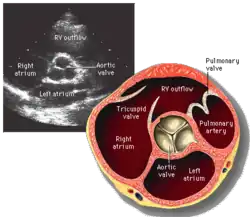

La evaluación del funcionamiento de la válvula aórtica puede hacerse de varias formas. La auscultación con un estetoscopio es rápida y fácil. La ecocardiografía transtorácica es una de las pruebas más útiles, puede cuantificar el grado de estenosis e insuficiencia y es posible determinar el grado de disfunción de la válvula. Otras pruebas menos empleadas son la ecocardiografía transesofágica, la resonancia magnética nuclear y la Tomografía axial computarizada.

La cuantificación de la velocidad máxima a través de la válvula, y el área de apertura, la existencia de calcificación, la morfología (tricúspide, bicúspide, unicúspide) y el tamaño de la válvula (anular, senos, unión sinotubular) son parámetros comunes al evaluar la válvula aórtica.